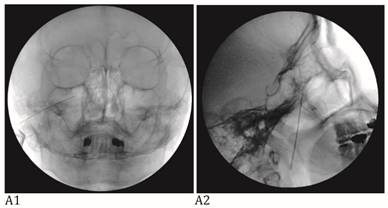

The Tnbs were performed with fluoroscopic guidance. Peripheral branch blocks including infraorbital nb (IONB) and supraorbital nb (SONB) and major branch blocks including maxillary nb (V2), mandibular nb (V3), and combined maxillary and mandibular nb (V2+3) were performed according to pain site of an individual patient. All study Tnbs were used pure alcohol (Dehydrated Alcohol Injection, USP, Tera Pharmaceuticals, Buena Park, CA, USA) after the confirming accurate needle position on the fluoroscopic view (Fig. 1) and diagnostic hypesthesia on the pain site using injection of 1% lidocaine with same doses of alcohol for neurolytic block. Total volume of alcohol for the Tnbs were; 0.3~0.5 ml for SONB, 0.5 ml for IONB, 0.5~1 ml for V2, 0.3~0.7 ml for V3, and 0.15~0.2 ml for V2+3.

Figure 1

A: Maxillary nerve block. A needle tip is located right lateral to foramen rotundum on the anteroposterior view (A1) and pterygopalatine fossa on the lateral view (A2). B: Mandibular nerve block. A needle tip is placed at the midportion of the foramen ovale on the anteroposterior oblique view (B1). At this point, a needle is advanced a few millimeters medially to elicit paresthesia in the V3 innervated area. When the proper paresthesia is achieved, a needle tip should be in a cross point of the lateral one-third of the perpendicular line and the midhorizontal line of the foramen ovale on the submentomandibular view (B2). On the lateral view, a needle is placed in the entrance of foramen ovale at the margin of petrous bone (B3). C: Combined maxillary and mandibular nerve block. A needle tip is placed at the midportion of the foramen ovale on the anteroposterior oblique view (C1). At this point, a needle is advanced a few millimeters cephalad passing foramen ovale on the submentomandibular view (C2). On the lateral view, a needle is placed passing foramen ovale a few millimeters under the clival line (C3).